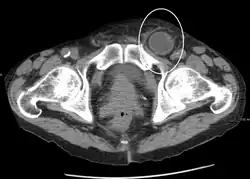

In the diagnosis of abdominal hernias, imaging is the principal means of detecting internal diaphragmatic and other nonpalpable or unsuspected hernias. Multidetector CT (MDCT) can show with precision the anatomic site of the hernia sac, the contents of the sac, and any complications. MDCT also offers clear detail of the abdominal wall allowing wall hernias to be identified accurately.[19]